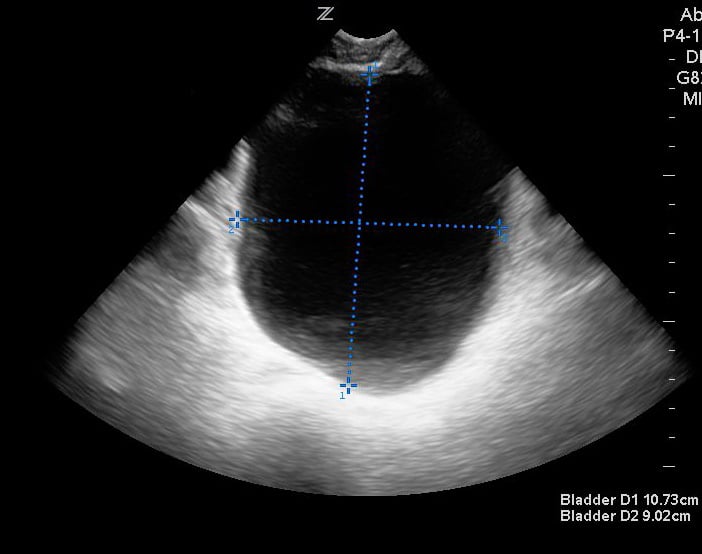

From www.researchgate.net

Sagittal and transverse view for measurement of urinary bladder volume How Do You Measure Bladder Volume On Ultrasound Some common uses of bladder. Refer to the text below the tool. A simple formula to remember and use is width x depth x height x. Estimates bladder volume based on ultrasound shape, length, width and height measurements. Bladder volume can be measured during an ultrasound (us) examination using the mathematical methods enumerated above. It shows you how to assess. How Do You Measure Bladder Volume On Ultrasound.